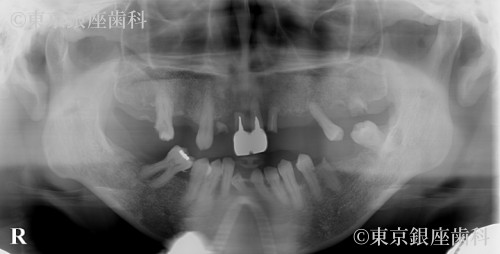

Before

疾患 歯牙部分欠損

幼少期からの歯科恐怖症で長期間治療を避けてきたが、家族の結婚式のため治療を決断。丁寧な説明で不安を軽減し、ワンデイインプラントで当日に仮歯を装着したことで自然な見た目で式に参加できた。

ワンデイインプラント(上下)